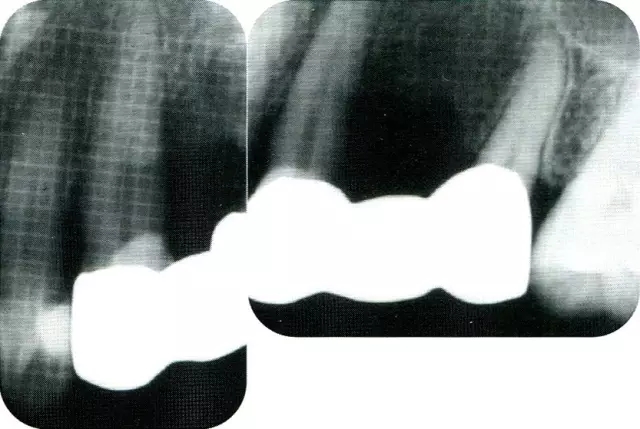

▲圖7-1  左下6近中可觀察到3壁性垂直性骨缺損。此病例考慮到齦瓣供血關(guān)系,在前磨牙部位進(jìn)行了減張切開,沒有進(jìn)行縱切開。并利用刮治器、牙周外科用車針進(jìn)行了徹底的骨缺損部位搔刮。

▲圖7-2  術(shù)前x片。確認(rèn)存在垂直性深骨缺損。